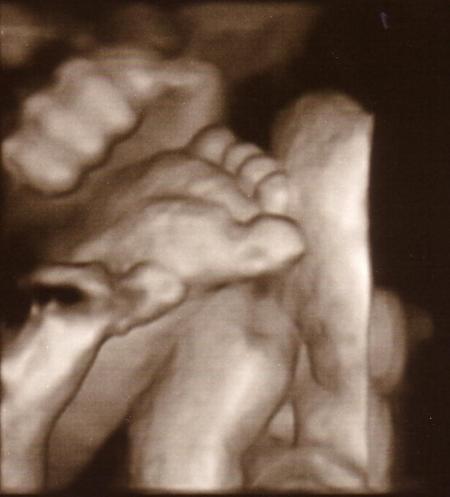

Kopf oben mitte-rechts, Hände und Füße vorm Gesicht, Popo unten links neben-unterhalb des Bauchnabels. Seeeeeeeeehr angenehm!

Bild zu